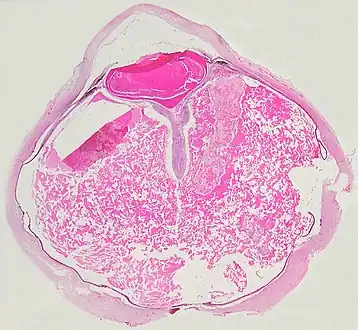

Coats' disease: histopathological findings, telangiectasic retinal vessels

Grossly, retinal detachment and yellowish subretinal exudate containing cholesterol crystals are commonly seen. Microscopically, the wall of retinal vessels may be thickened in some cases, while in other cases the wall may be thinned with irregular dilatation of the lumen.[10] The subretinal exudate consists of cholesterol crystals, macrophages laden with cholesterol and pigment, erythrocytes, and hemosiderin.[11] A granulomatous reaction, induced by the exudate, may be seen with the retina.[12] Portions of the retina may develop gliosis as a response to injury.